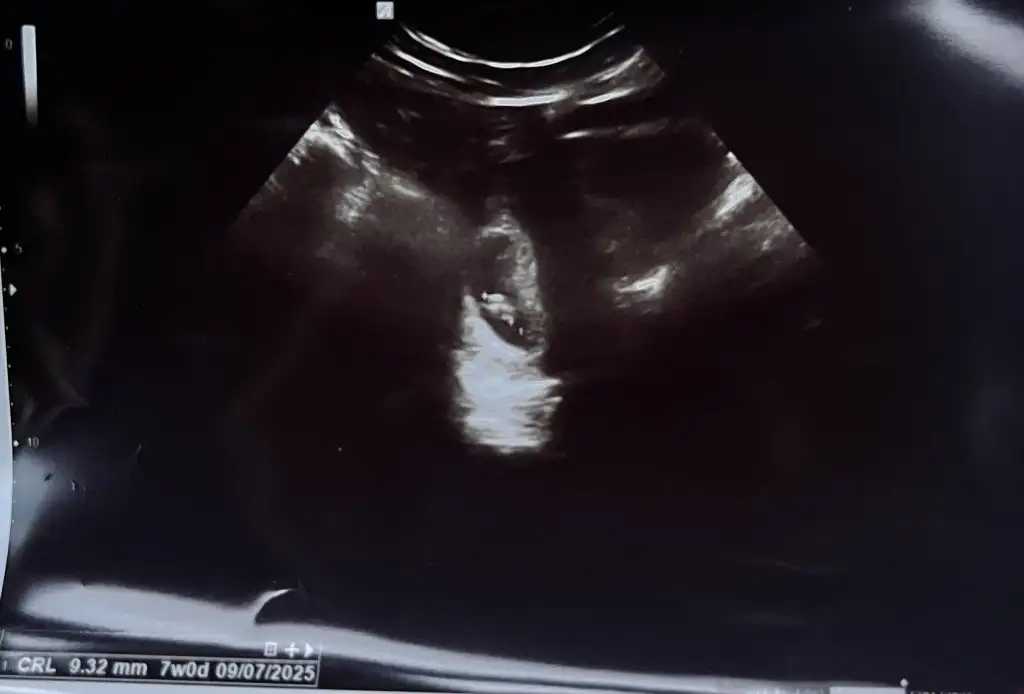

Daha küçük yaRica etsem bana da tahmin de bulunabilir misiniz burada 7 haftalıktı